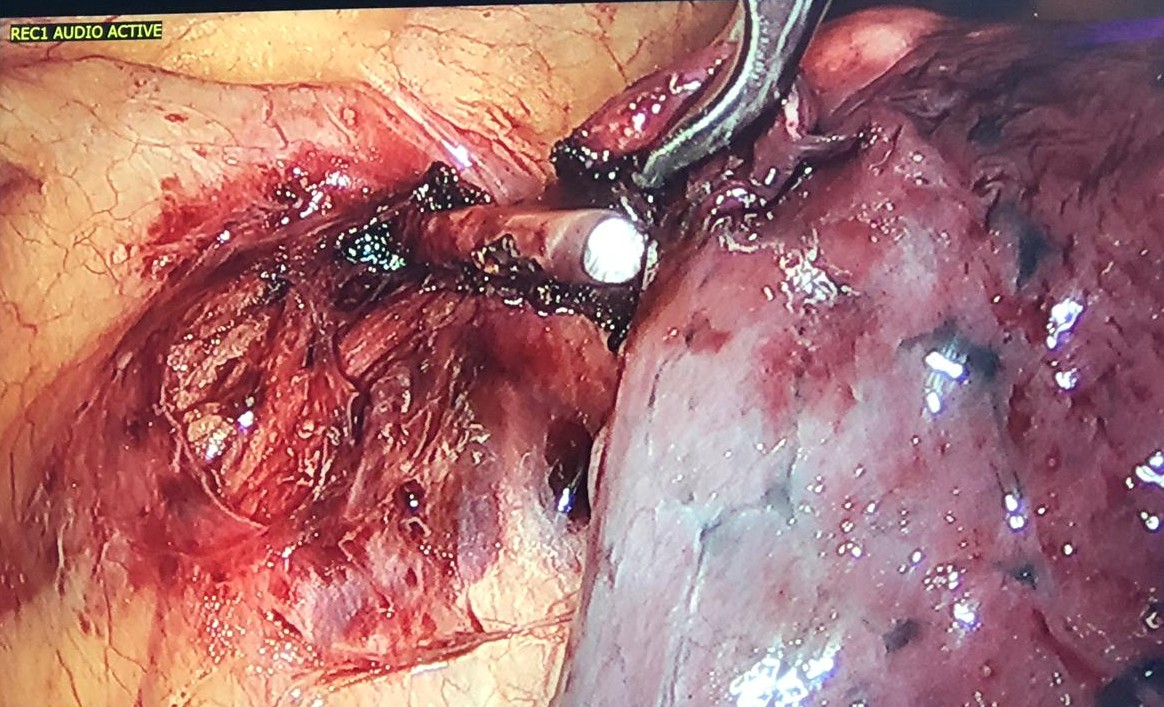

Figure 5. Left upper lobe dissected free from the mediastinal pleura, with care to preserve the left phrenic nerve. The part of the lung still adherent to the mediastinum corresponds to the K-wire penetrating the lung.

Figure 6. K-wire completely dissected from the lung. One can observe the phrenic nerve very close to the K-wire.

Figure 7. With the aid of an energy device, the authors dissected the tissues around the foreign body, in front of the phrenic nerve like in a thymectomy, and the K-wire was easily removed. It was not hooked to the left brachiocephalic vein.